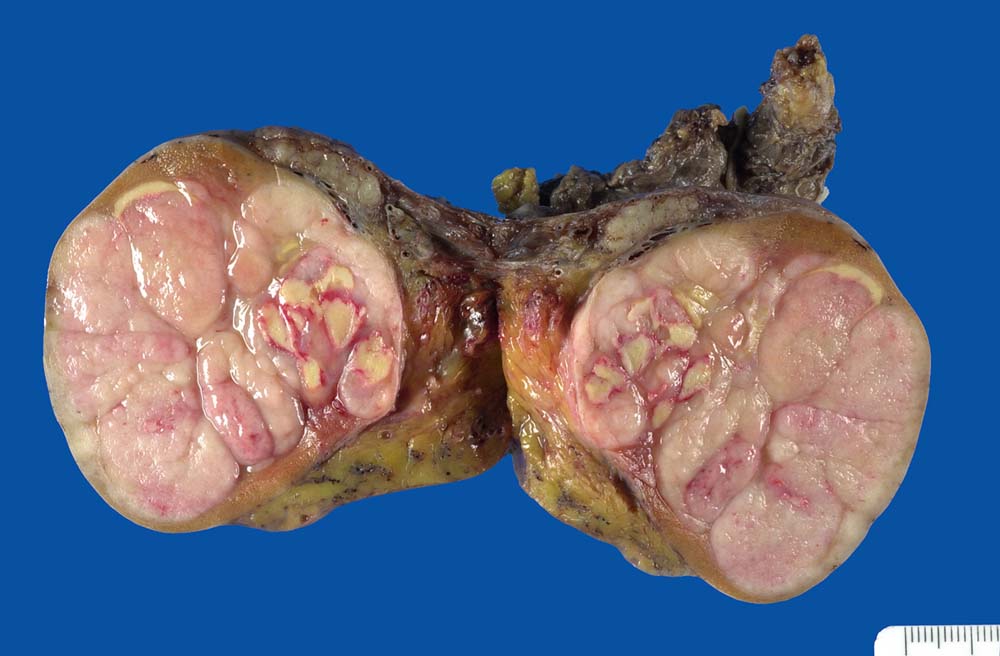

Makroskopisch imponieren Seminome als gut begrenzte weiche crèmefarbene Knoten oder diffuses Intiltrat. Mikroskopisch findet sich eine uniforme Population grosser Zellen mit prominentem zentralem Nukleolus, welche durch schmale Bindegewebssepten voneinander getrennte Nester bilden. Ein leukozytäres Entzündungsinfiltrat, synzytiotrophoblastäre Riesenzellen und Mikroverkalkungen können zusätzlich vorhanden sein. Gelegentlich induziert der Tumor eine ausgeprägte granulomatöse Entzündung. Dies kann zur Fehldiganose einer granulomatösen Orchitis führen.

• Scharf begrenzter Tumorknoten mit eosinophilen Nekrosearealen.

• Unterschiedlich breite solide Tumorzellstränge aus monomorphen Zellen mit grossen hyperchromatischen Kernen und einem solitären zentralen prominenten Nukleolus. Reichlich helles Zytoplasma mit scharfen Zellgrenzen.